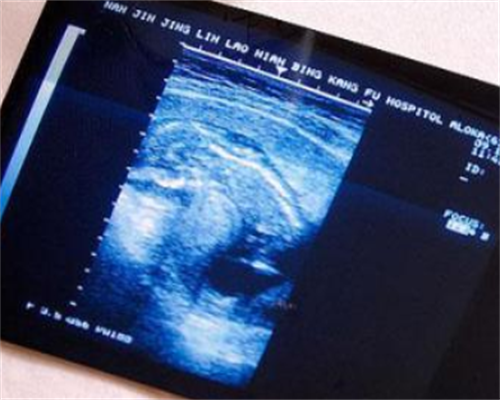

3号去医院测了一次,6号再测了一次,显示还没有排卵,于是医生建议四天后再去测。当时因为6号开始就不测核酸了,担心多,去医院不安全,就没有再去医院了。 自己在家尽快控制少喝水,有尿就测的原则。于9号下午和10号测到强阳。从测到强阳之前到后面转弱都有安排。7hW泰国试管婴儿医院费用-流程-成功率 - 南方海外